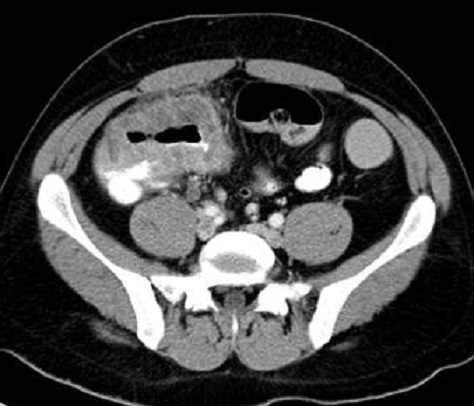

| Image radiologique TDM

en coupe axiale d'une carcinome colloide ( mucinous

carcinoma )du colon ascendant . La

difference de carcinome colloide est image de

epaissise irreguliairement non stenosant d'une

portion du colon . |

Adenocarcinome du caecum :

Mass hyper-dense en bourgeonante non

homogene du caecum ( fleche rouge ) . Image

radiologique TDM en coupe coronale . |